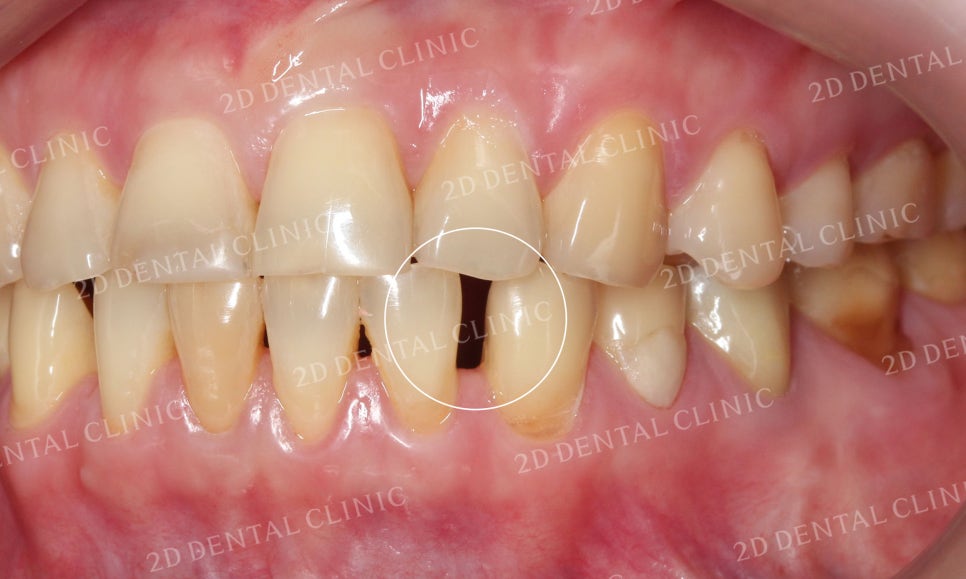

블링스 시술 전 환자분의 치아 상태는

치아가 전체적으로 누렇게 착색되어 있고

잇몸의 퇴축으로 인해 치아 뿌리들이 조금씩

드러나고 있는 상황이었습니다.

또한 치아 사이의 공간이 있어서

치간이개로 인한 블랙트라이앵글도

발견되었고요.

심미적으로도 좋지 못하고,

환자분께서도 약해진 잇몸과 치아때문에

스트레스를 받고 계셨습니다ㅠ

블링스 시술 전후 전치부의 사진입니다.

잇몸의 퇴축으로 치아 사이에 빈틈이 보이던

시술 전과 달리 시술 후 치아가 예쁘게 자리잡힌 모습이네요~